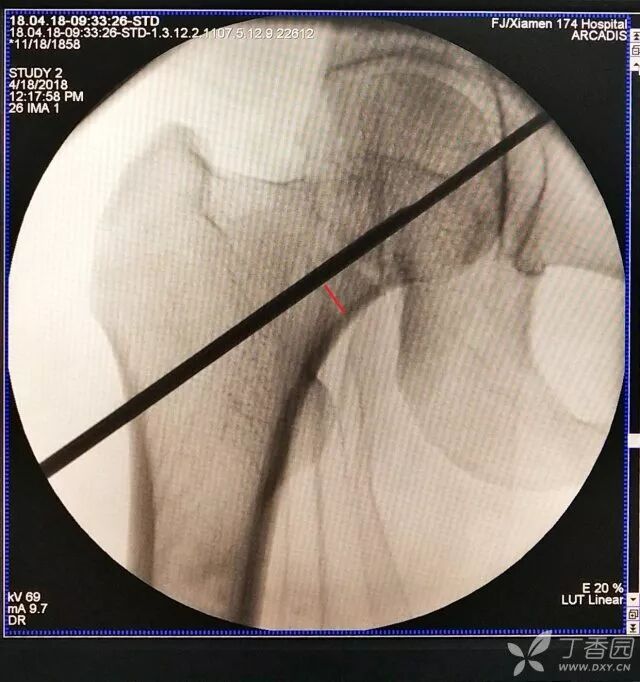

2. 倒数第二次的复位仍是欠缺一点

牵引床怎么用视频详解:如何不使用牵引床做好一台股骨颈骨折?_https://www.jmylbn.com_新闻资讯_第10张

3. 再努力一把就基本成了

牵引床怎么用视频详解:如何不使用牵引床做好一台股骨颈骨折?_https://www.jmylbn.com_新闻资讯_第11张